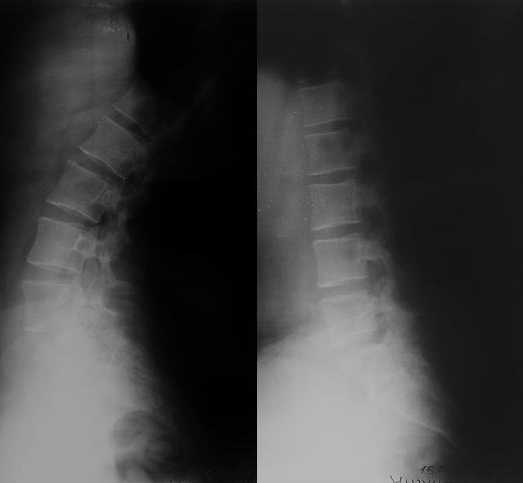

13/03/03 |  13/03/03 |  13/03/03 |  15/09/06 |  15/09/06 |  07/03/07 |  07/03/07 |  19/12/06 | К нам в клинику поступила пациентка 30 лет с диагнозом: Постравматическая ротационная стабильная деформация тазового кольца. Относительное укорочение левой н\конечности на 1 см. Левосторонний компенсаторный сколиоз 2 ст. Болевой синдром. травма автодорожная в январе 2003г. Пассажирка переднего сидения ваз 2109. лечились положением по Волковичу. С марта 2003 года жалуется на боли в тазу, ппояснице усиливающиеся при движении.В настоящее время жалобы на боли в области крестца, КПС больше слева, в пояснично-крестцовом отделе позвоночника. неприятные ощущения, щелчок при выпрямлении правого тазобедренного сустава из положения полного сгибания. боли в тазу появляются при ходьбе ч\з 100 м, так же при вставании из положения сидя, после сидения в течении 2-3 часов. при ходьбе более 100 м появпяется зябкость стоп больше справа. ходит при помощи трости в правой или в левой руке. без трости боли появляются сразу после начала ходьбы. пальпация болезненна в паравертебральных точках средне-грудного и пояснично-крестцового отделов позвоночника, КПС с обеих сторон. Объем движений в тазобедренных суставах полный.правый КПС заблокирован. симптомы натяжения с обеих сторон отрицательны.С 2003г. лечится консервативно, получала ЛФК, массаж, физиолечение - без эффекта. в 2005г. лечилась в санатории с ортопедическим уклоном, получала плавание в минеральной воде, магнитотерапия, массаж, ЛФК. отмечала умеренное улучшение в течении 2 недель.Вопросы:надо ли оперировать, т.е. устранять относительное укорочение левой н\конечности и как?Если не оперировать, то как лечить консервативно?Р-граммы, КТ прилогаются.

Проблема Вашей пациентки находится на границе интересов специальностей ортопедия (вертебралогия) и неврология (нейрохирургия), вероятно, поэтому так мало откликов на ваше обращение. Представленные рентгенограммы не все информативны (особенно спондилограммы от сентября 2006 года). Вероятно, необходимы дополнительные методы исследования к.т. МТГ, ЯМРТ, миелография.

просьбе. досылаю КТ, фуккциональные Р-граммы пояснично-крестцового отдела позвоночника, фото пациентки.

Уважаемый Максим. Снимки от 7.03.07 и есть функциональные, т.е. стоя на правой, и левой ноге.

Здравствуйте уважаемые коллеги. Высылаю обещаннное ЯМРТ. Никаких нарушений м\позвонковых дисков, мяггкотканных образований на уровне Th12-S3 не обнаружено.